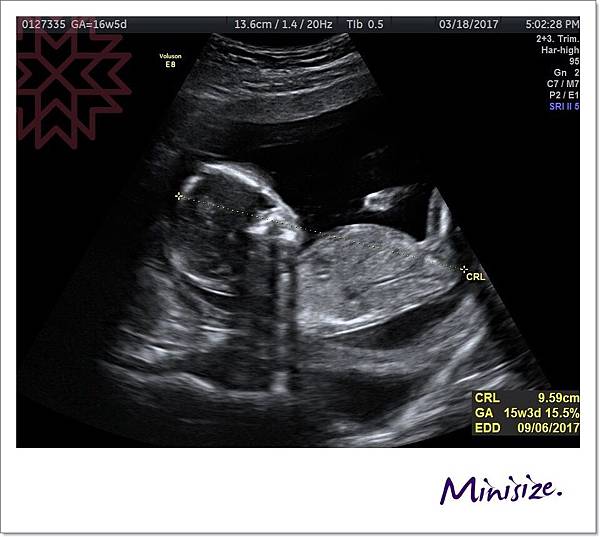

醫生細心解說

頭圍、頭臀圍、腿長、腦發育、心跳聲、子宮頸長度、羊水是否充足

才了解到原來我的大肚皮裡面藏一個頭臀圍長9.59公分的健康寶寶

聽到寶寶鏗鏘有力的心跳

真的好感動

小生命正在努力地長大中!